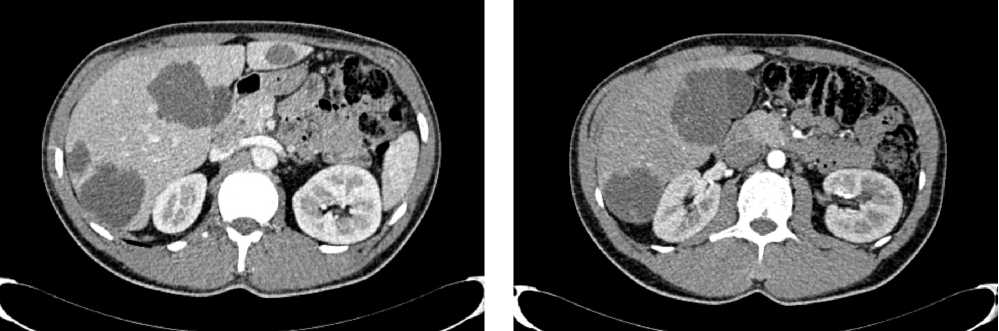

По решению онкологического консилиума пациенту начат ПХТ 1 линии в режиме FOLFOX + бевацизумаб. С 02.09.2022 проведено 3 цикла ПХТ 1 линии, по результатам контрольных обследований зарегистрировано прогрессирование процесса за счет роста образований печени до 64 × 46 мм и появления линзовидного образования между передней поверхностью прямой кишки и задней поверхностью предстательной железы размерами 47 × 15 × 25 мм (рис. 7, 8).

Рис. 7. Результаты компьютерной томографии органов брюшной полости у пациента 37 лет с диагнозом метастатический колоректальный рак с признаками микросателлитной нестабильности (октябрь 2022 г., после 3-х циклов FOLFOX + бевацизумаб)

Fig. 7. Results of abdominal CT scan in a 37-year-old patient diagnosed with metastatic MSI-H colorectal cancer (October 2022, after 3 cycles of FOLFOX + bevacizumab)

Рис. 8. Результаты магнитно-резонансной томографии органов брюшной полости у пациента 37 лет с диагнозом метастатический колоректальный рак с признаками микросателлитной нестабильности (октябрь 2022 г., после 3-х циклов FOLFOX + бевацизумаб)

Fig. 8. Results of abdominal MRI in a 37-year-old patient diagnosed with metastatic MSI-H colorectal cancer (October 2022, after 3 cycles of FOLFOX + bevacizumab)

В октябре 2022 г. получены результаты иммуногистохимического исследования на предмет MSI, выявлена утрата ядерной экспрессии MLH1 и PMS2.

С учетом результатов ИГХ, прогрессирования процесса по результатам контрольных обследований, пациенту начата 2 линия системного лечения пембролизумабом в монорежиме.

С ноября 2022 г. выполнено 14 введений пембролизумаба с максимальным эффектом частичный регресс (образование между передней поверхностью прямой кишки и задней поверхностью предстательной железы регрессировало полностью). По результатам контрольных обследований (КТ ОБП и МРТ ОМТ от сентября 2023 г.) сохраняются очаги в печени до 21 × 11 мм, а также опухоль средне- и верхнеампулярного отделов прямой кишки с выраженным муцинозным компонентом. МР-стадия Т4а (CRM+, EMVI+) (рис. 9, 10).

Рис. 9. Частичный регресс, по данным компьютерной томографии органов брюшной полости, на фоне иммунотерапии пембролизумабом у пациента 38 лет с диагнозом метастатический колоректальный рак с признаками микросателлитной нестабильности (сентябрь 2023 г.)

Fig. 9. Partial response according to abdominal CT scan data during immunotherapy with pembrolizumab in a 38-year-old patient with metastatic MSI-H colorectal cancer (September 2023)